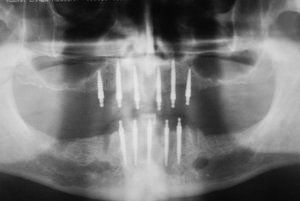

At Dental Innovations in Wasilla, AK, we can fit the very latest implant supported dentures, implant retained dentures, or more complex or targeted solutions for a particular patient situation. Contact our team today to arrange a consultation.